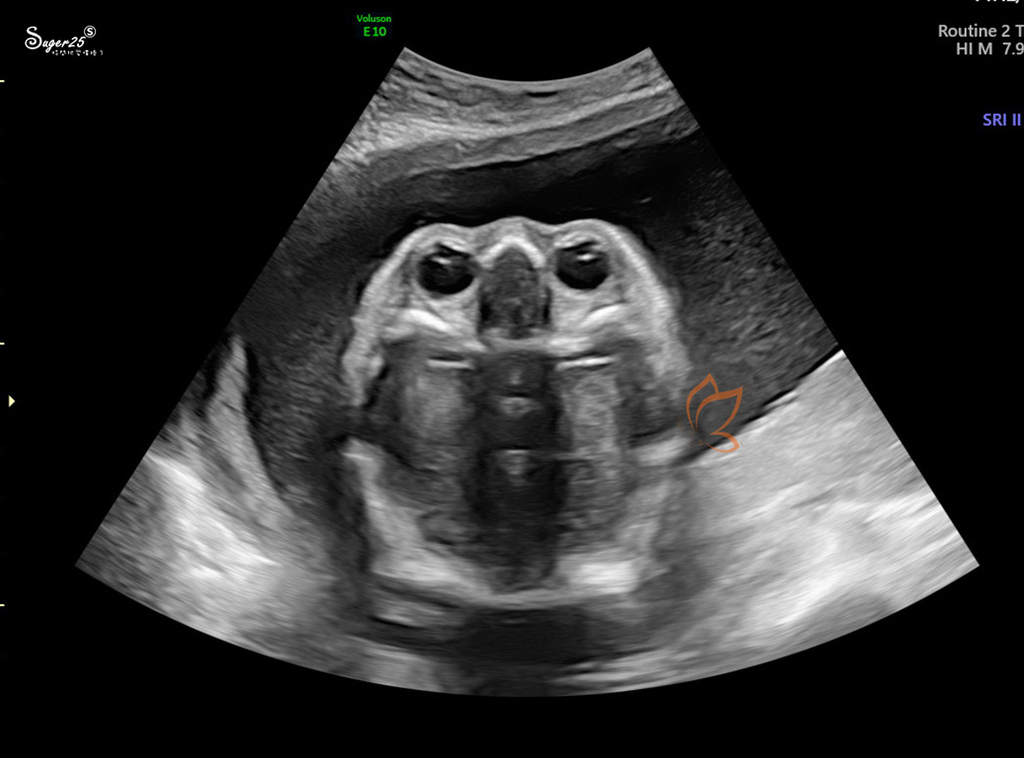

這張好像蒼蠅 哈哈哈哈哈 是五官